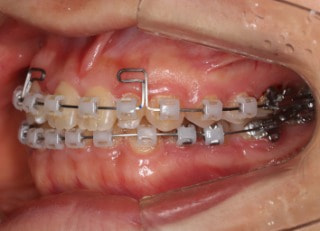

治療開始から25ヶ月後